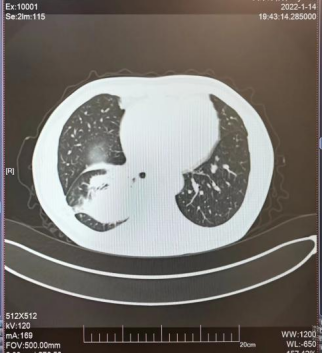

2022年1月,患者的胸部CT提示肺部腫瘤較前明顯增大(見圖5),檢測(cè)血清腫瘤標(biāo)志物結(jié)果于是便出現(xiàn)前面所提到的一幕(患者的神經(jīng)元特異性烯醇化酶(NSE)高達(dá)125.30ng/ml)。再次行肺穿刺活檢病理診斷為具有大細(xì)胞特征的高級(jí)別神經(jīng)內(nèi)分泌癌(見圖6),治療方案馬上更改為化療+免疫治療。經(jīng)上述治療后患者一般情況明顯好轉(zhuǎn),復(fù)查胸部CT示肺部腫瘤病灶明顯縮小。。

圖5 2022-1胸部CT圖